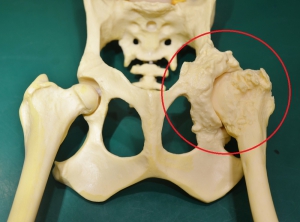

下の写真は股関節の重度の変形性関節症をしめす骨格モデルです。画面左の赤丸の中が重度に変形した関節構造をモデル化したものです。真ん中が正常な股関節で右がその部位の重度の変形関節症(拡大)です。